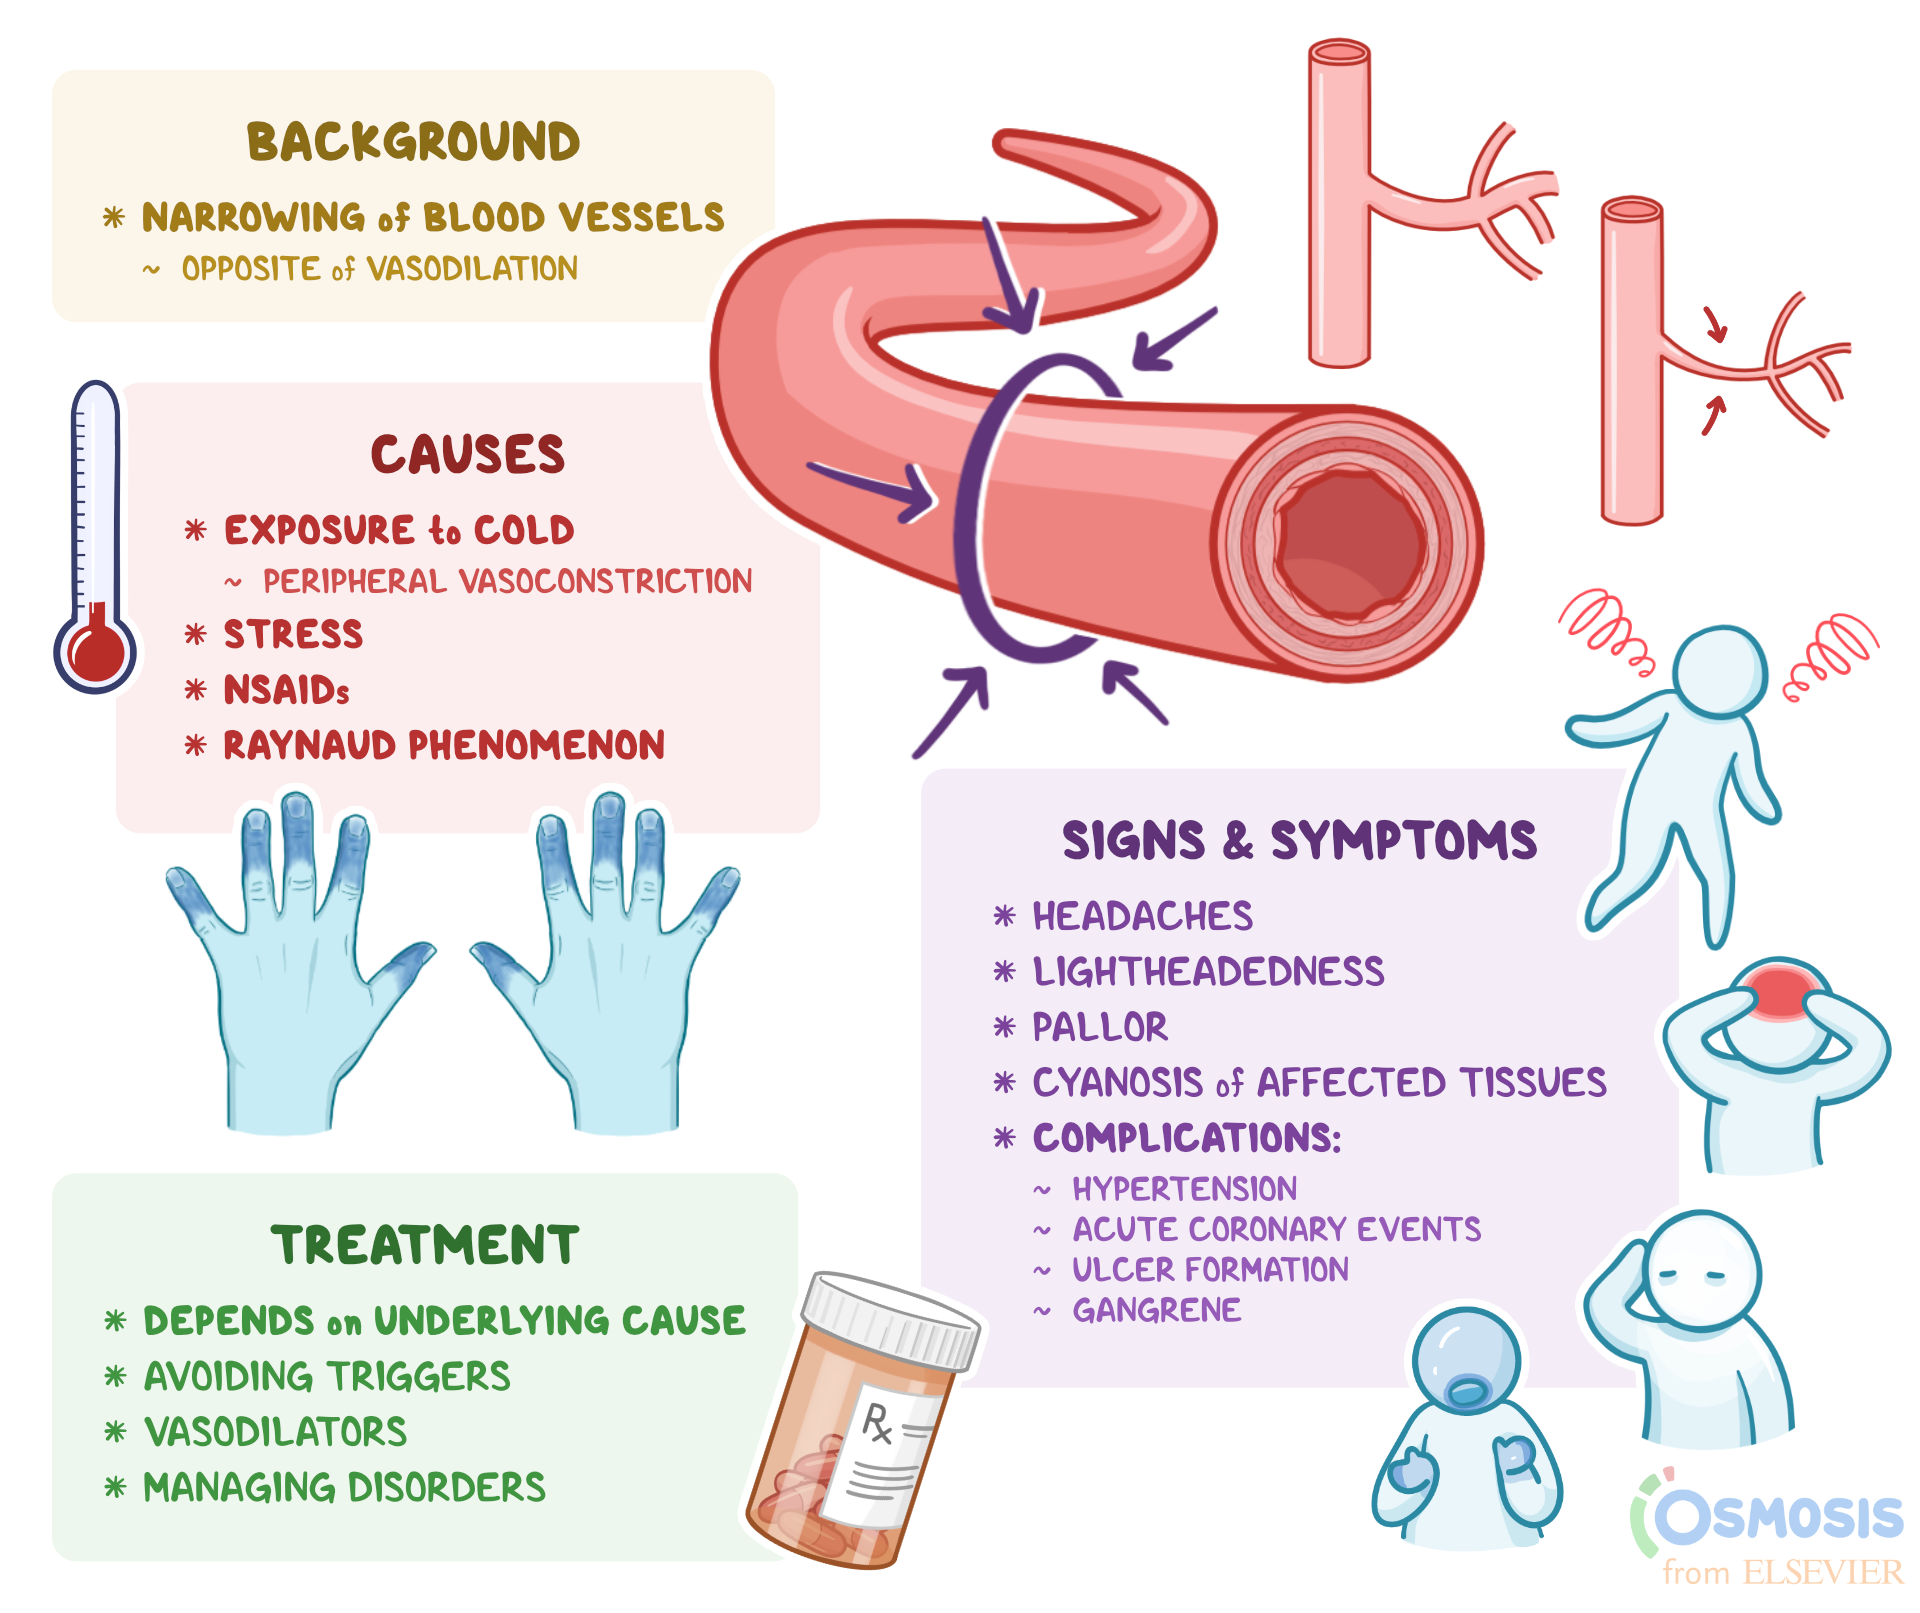

Vasoconstriction What Is It Causes Signs Symptoms And More Osmosis

https://d16qt3wv6xm098.cloudfront.net/D8yIIlmWS6mLb4SZUBAMzv5DQR2LErX5/_.png